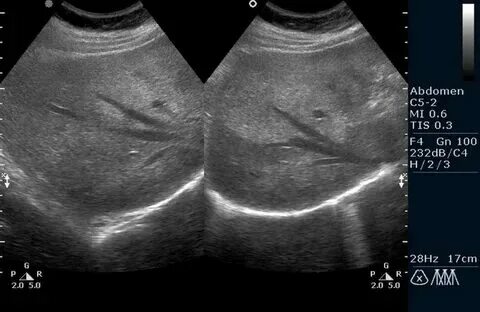

Диффузно неоднородное изменение синусов почек